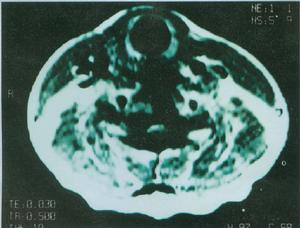

3、CT檢查 在CT掃描圖上胰假性囊腫為邊緣光滑的圓形或卵圓形密度均勻減低區。如CT檢查顯示有氣液平面,說明有感染性膿腫形成。